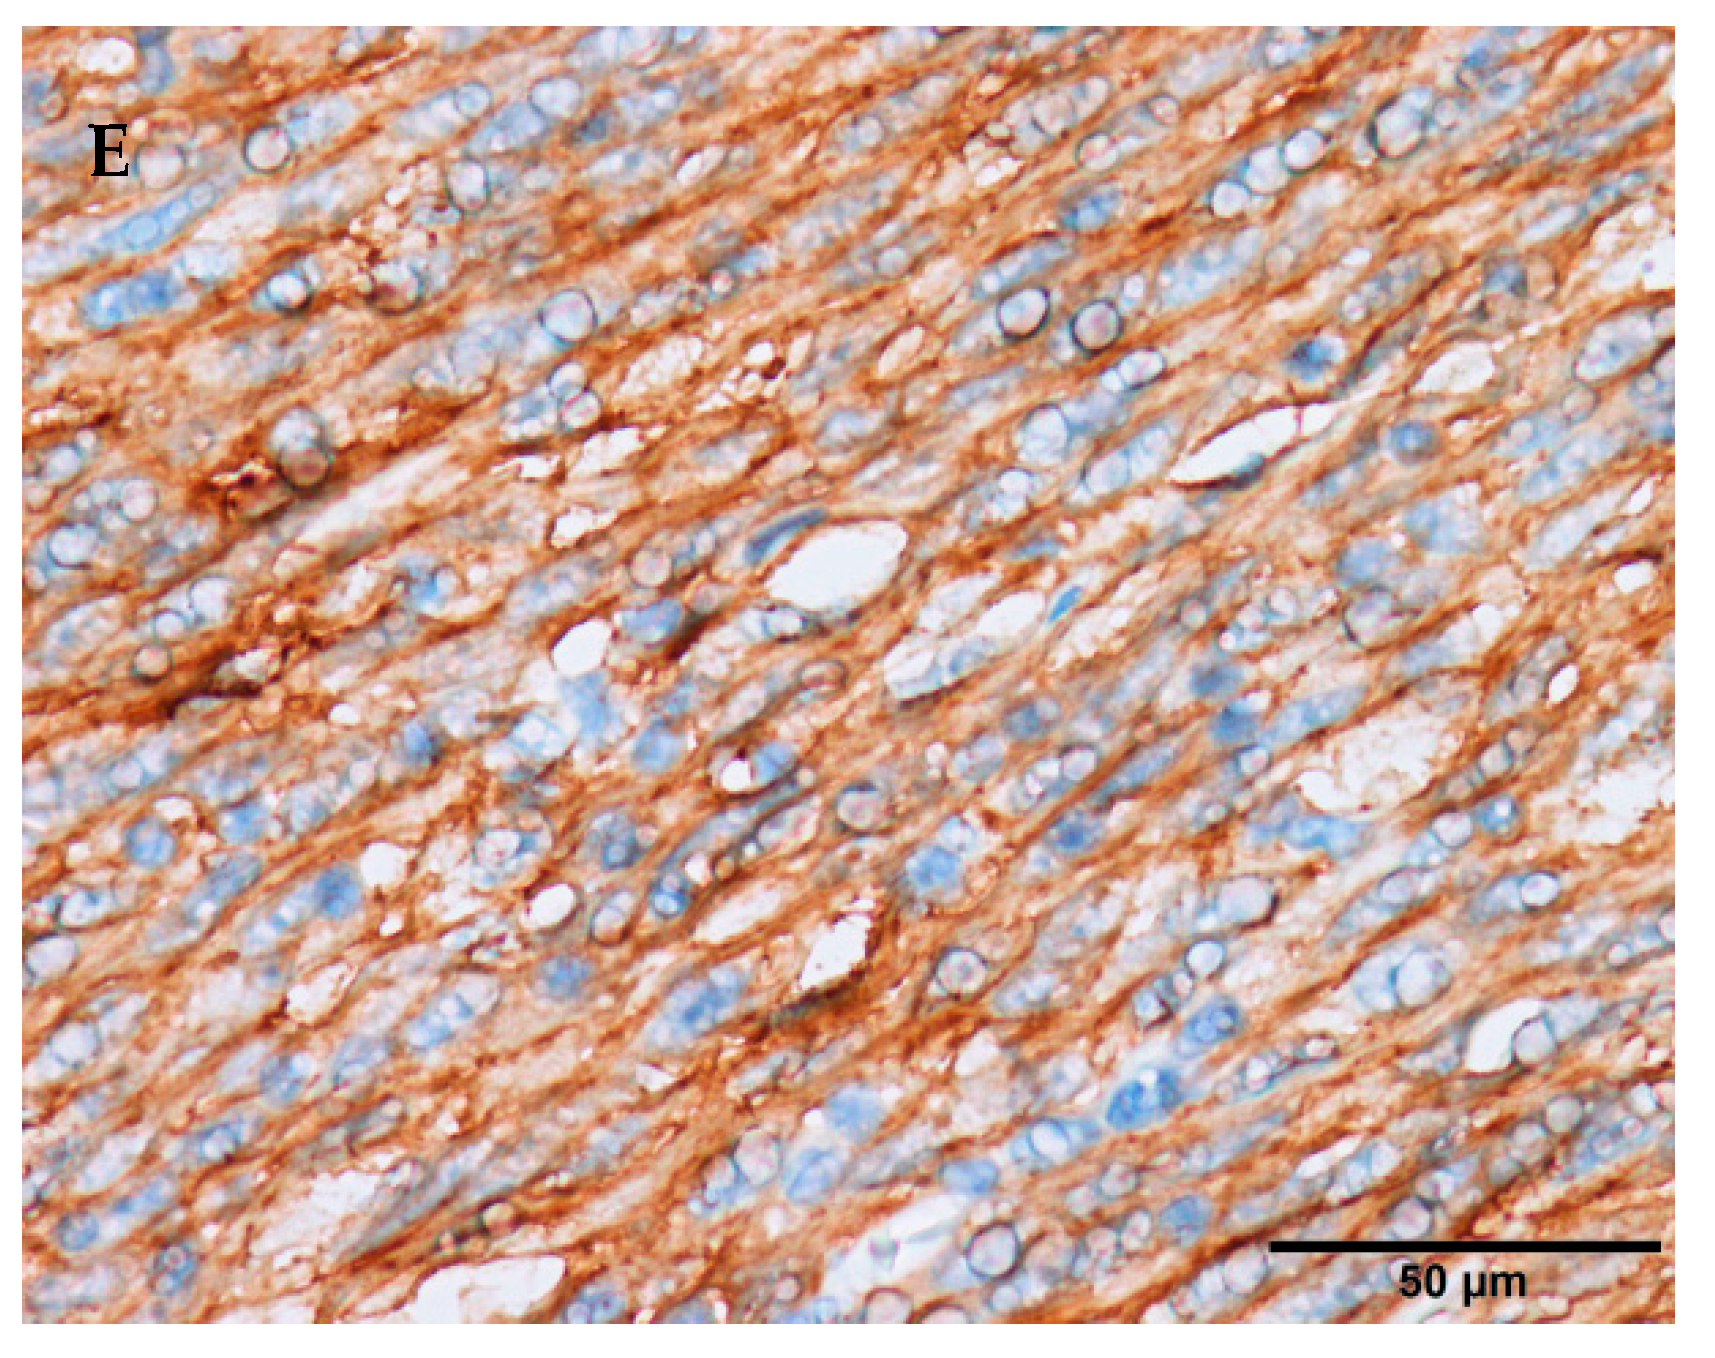

- Novelli, M.; Rossi, S.; Rodriguez-Justo, M.; Taniere, P.; Seddon, B.; Toffolatti, L.; Sartor, C.; Hogendoorn, P.C.; Sciot, R.; Van Glabbeke, M. DOG1 and CD117 are the antibodies of choice in the diagnosis of gastrointestinal stromal tumours. Histopathology 2010, 57, 259–270. [Google Scholar] [CrossRef]

- Miettinen, M.; Wang, Z.F.; Lasota, J. DOG1 Antibody in the Differential Diagnosis of Gastrointestinal Stromal Tumors: A Study of 1840 Cases. Am. J. Surg. Pathol. 2009, 33, 1401–1408. [Google Scholar] [CrossRef] [PubMed]